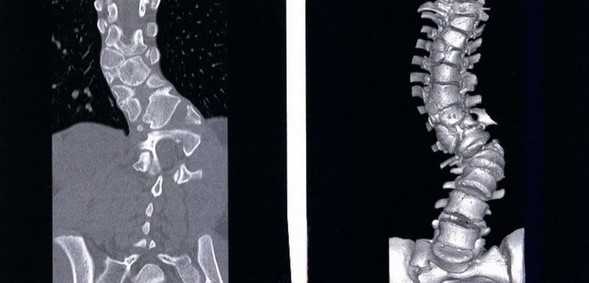

Компрессионный перелом (показан стрелкой) поясничного отдела позвоночника

При развитии патологического процесса возникают структурные нарушения, аномалии формы и размеров морфологических элементов.

Трещина (показана стрелкой) тела позвонка